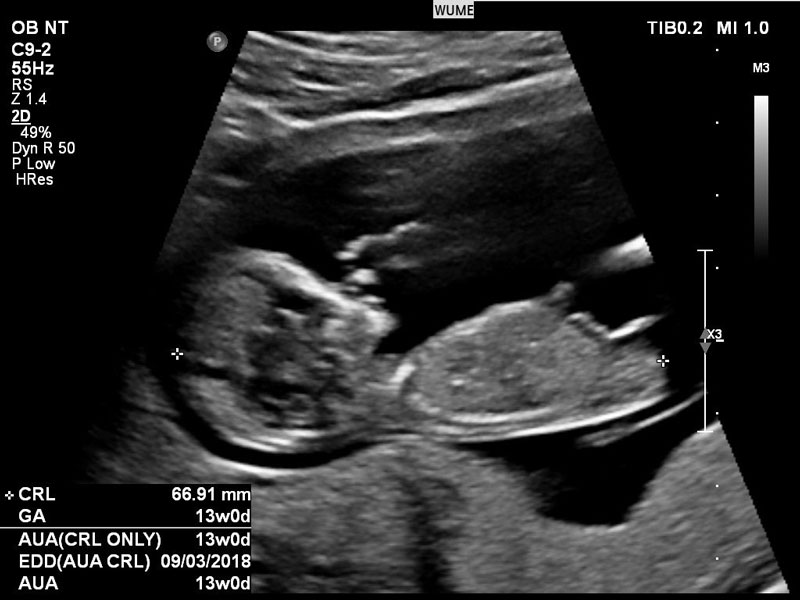

Ý nghĩa của các chỉ số trong tờ giấy siêu âm

Có rất nhiều các thuật ngữ cho biết chỉ số phát triển của thai nhi. Dưới đây là một vài thuật ngữ và chữ cái viết tắt của các chỉ số thai nhi quan trọng cho mẹ bầu tham khảo:

- GA: số tuổi của thai tính từ ngày đầu tiên của chu kỳ kinh cuối cùng.

- CRL: chiều dài đầu mông.

- BPD: đường kính lưỡng đỉnh, đường kính to nhất được đo ngang qua xương thái dương theo bề ngang.

- FL: độ dài xương đùi.

- EFW: ước tính số cân của thai nhi.

- TTD: đường kính đo ngang bụng.

- APTD: đường kính đo ở trước và phía sau bụng của thai.

- HC: chu vi của đầu thai nhi.

- AC: chu vi của vòng bụng.

- AF: nước ối.

- AFI: chỉ số nước ối.

- OFD: đường kính của xương chẩm, được đo tại mặt cắt to nhất tính từ trán ra phía sau gáy hộp sọ của bé.

- EDD: ngày sinh dự đoán.